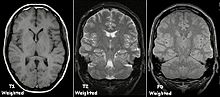

Each tissue returns to its equilibrium state after excitation by the independent relaxation processes of T1 (spin-lattice; that is, magnetization in the same direction as the static magnetic field) and T2 (spin-spin; transverse to the static magnetic field). To create a T1-weighted image, magnetization is allowed to recover before measuring the MR signal by changing the repetition time (TR). This image weighting is useful for assessing the cerebral cortex, identifying fatty tissue, characterizing focal liver lesions, and in general, obtaining morphological information, as well as for post-contrast imaging. To create a T2-weighted image, magnetization is allowed to decay before measuring the MR signal by changing the echo time (TE). This image weighting is useful for detecting edema and inflammation, revealing white matter lesions, and assessing zonal anatomy in the prostate and uterus.

The standard display of MRI images is to represent fluid characteristics in black and white images, where different tissues turn out as follows:

An MRI sequence is a particular setting of radiofrequency pulses and gradients, resulting in a particular image appearance.[52] The T1 and T2 weighting can also be described as MRI sequences.

| Spin echo | T1 weighted | T1 | Measuring spin–lattice relaxation by using a short repetition time (TR) and echo time (TE). |

Standard foundation and comparison for other sequences |

| T2 weighted | T2 | Measuring spin–spin relaxation by using long TR and TE times |